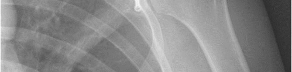

Question 15:

A 20-year-old collegiate swimmer presents with bilateral shoulder pain. On physical examination, she demonstrates a positive sulcus sign and apprehension in abduction/external rotation, but she is able to voluntarily dislocate and reduce her shoulders without pain. She has no history of an acute traumatic dislocation. Which of the following is the most appropriate initial management?

Correct Answer: Physical therapy emphasizing periscapular and rotator cuff strengthening

Explanation:

This patient exhibits classic signs of atraumatic, multidirectional instability (MDI), often characterized by the AMBRI acronym (Atraumatic, Multidirectional, Bilateral, Rehabilitation, Inferior capsular shift). The hallmark of treatment for MDI is a prolonged, dedicated physical therapy program focusing on strengthening the dynamic stabilizers of the shoulder (rotator cuff and periscapular muscles). Surgery (inferior capsular shift) is reserved for patients who fail extensive conservative management.